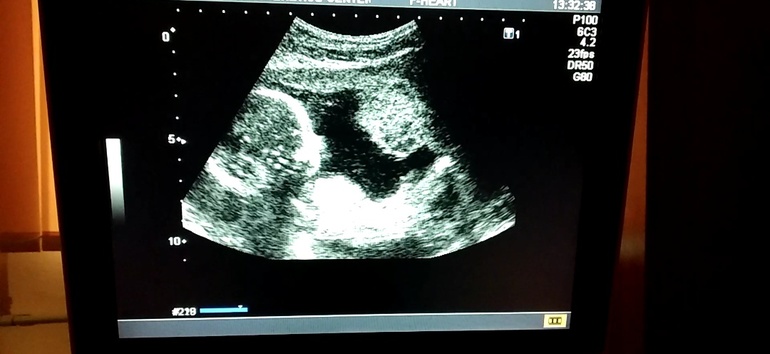

Изменения и болезни во время БМы узнали 11 сентября, что у нас будет сын, честно положа руку на сердце, хотели с мужем именно мальчика :)) с 16 недель активно пинаем маму🐒🐒, по УЗИ все ттт хорошо. Фоточка на память есть, даже видео сняли, где малютик пинается 😊